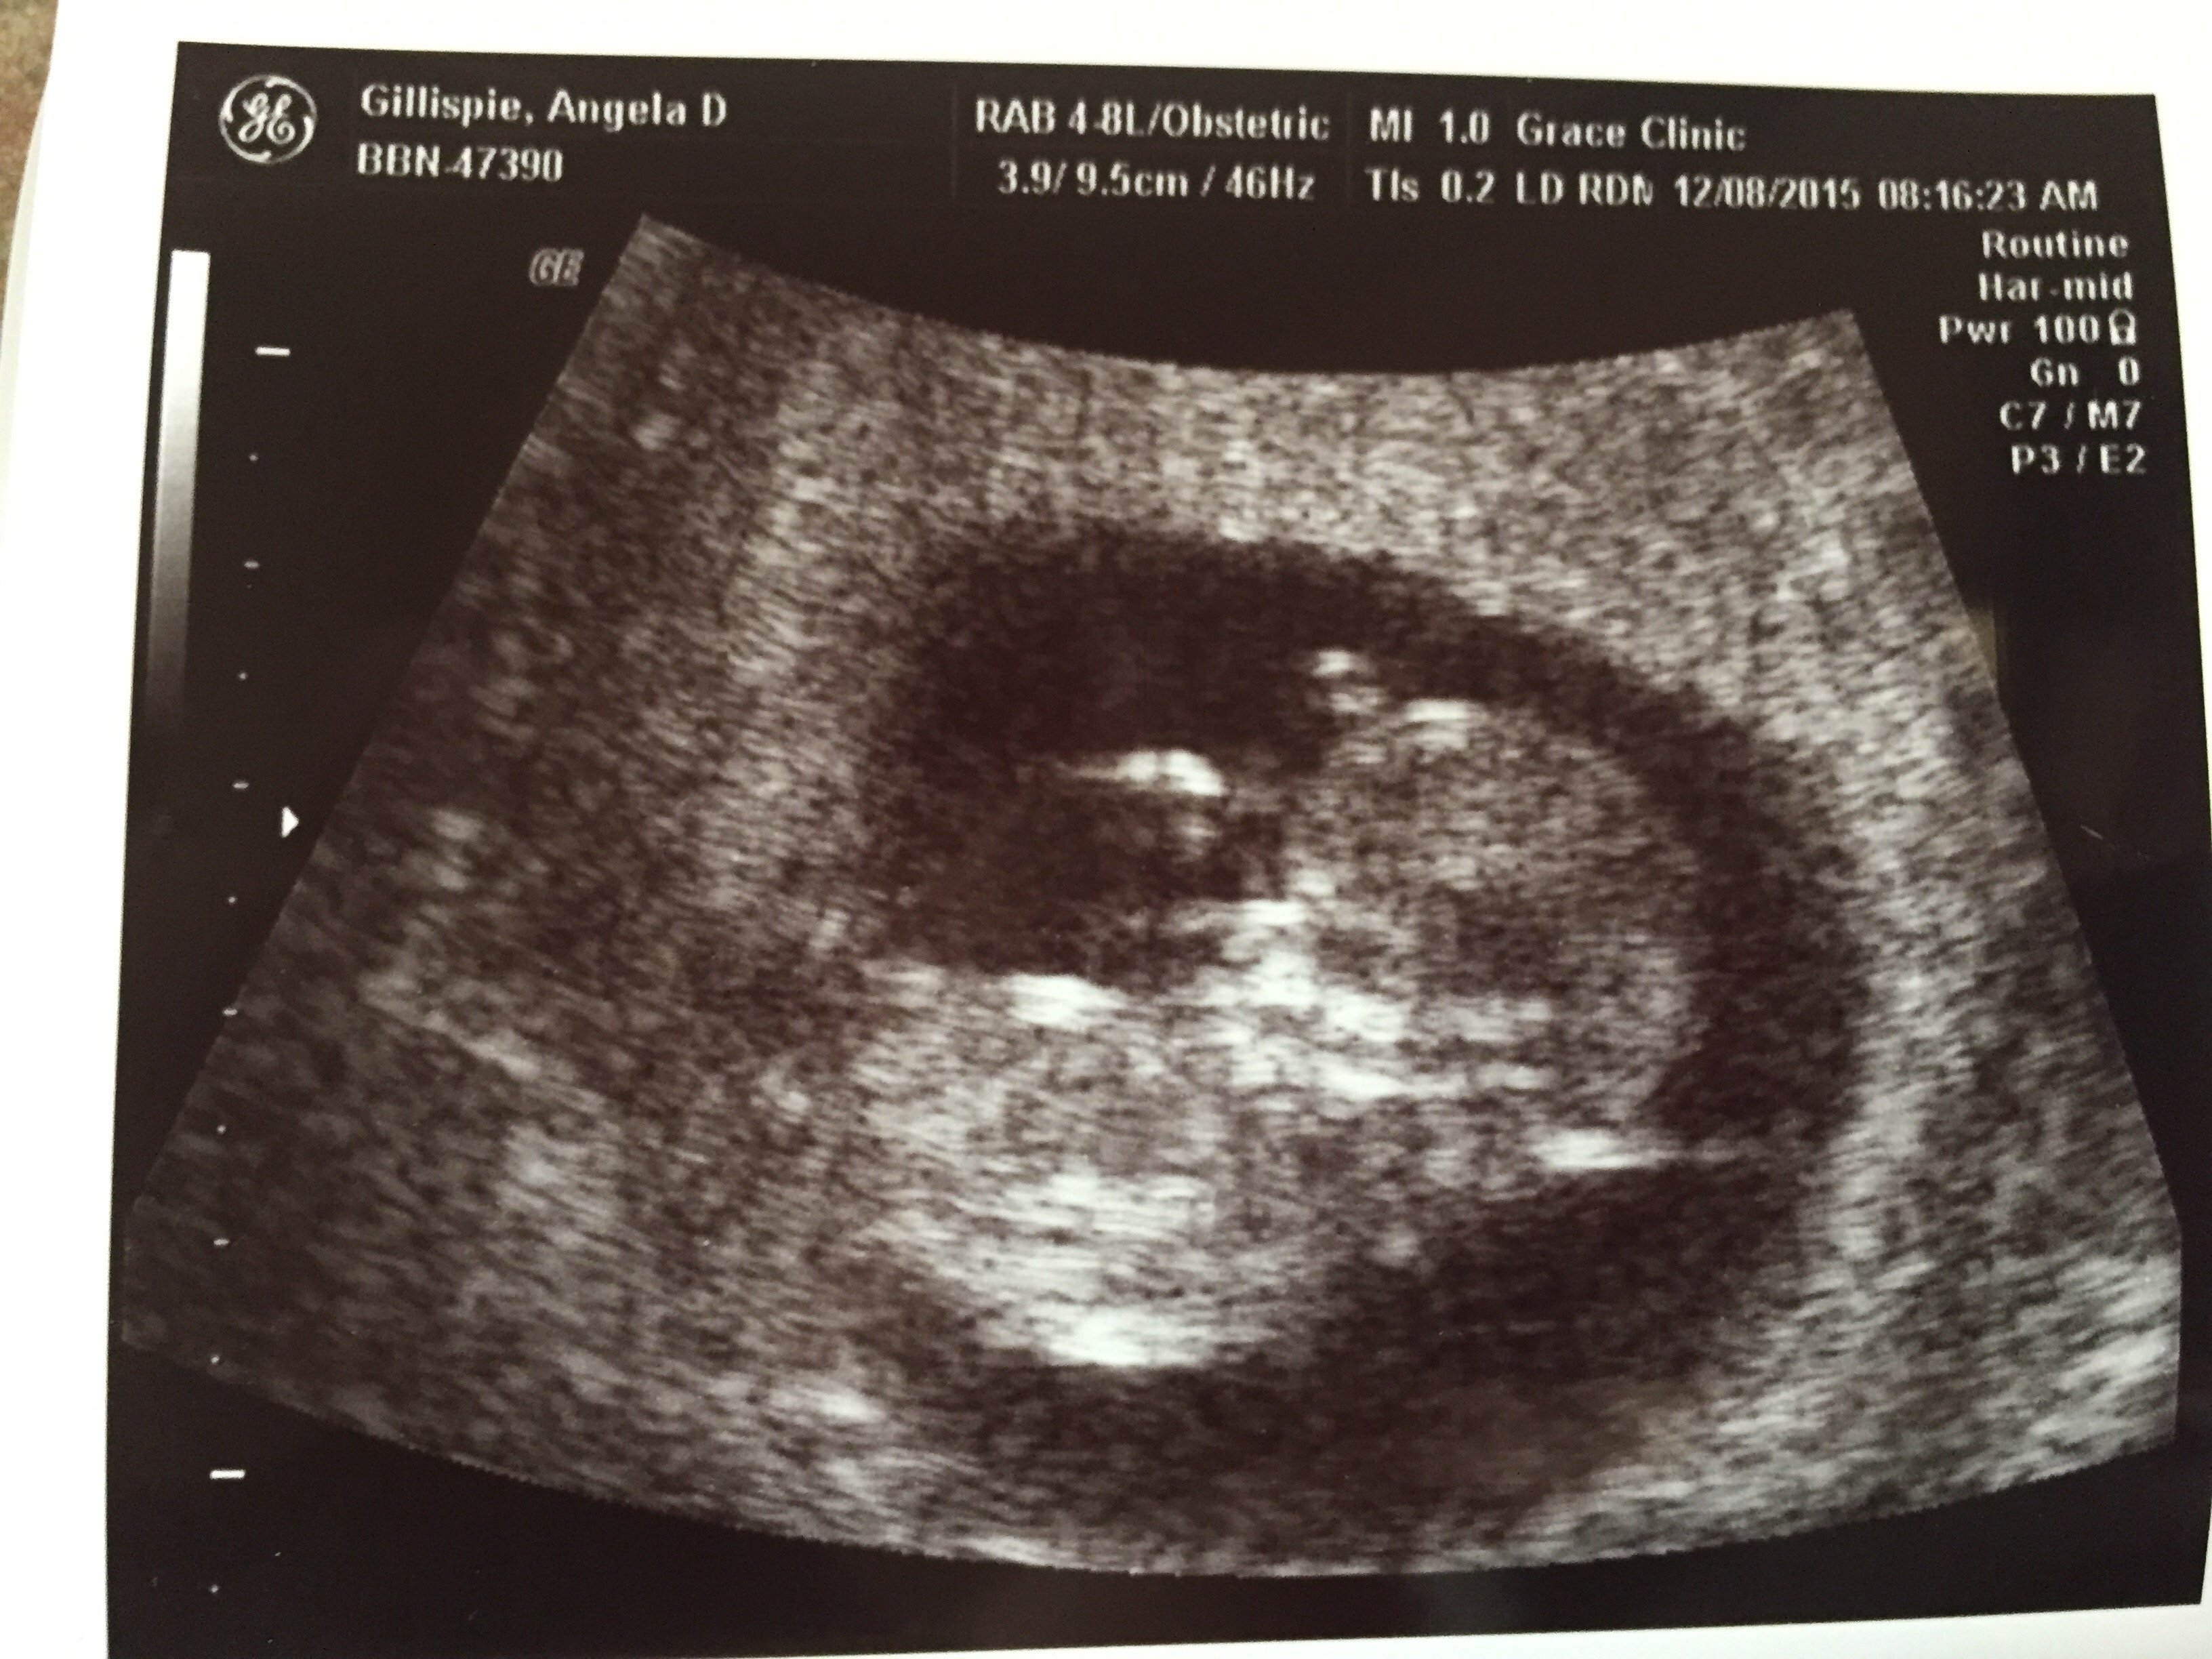

My midwife is so awesome!! After our initial appointment today she pulled out the ultrasound machine so we could have a quick look at our peanut. This baby is super active, would barely hold still long enough for a picture. Our midwife enjoyed it as much as we did. I am measuring 2 days ahead at 11 weeks 4 days, but not enough to move up my due date.